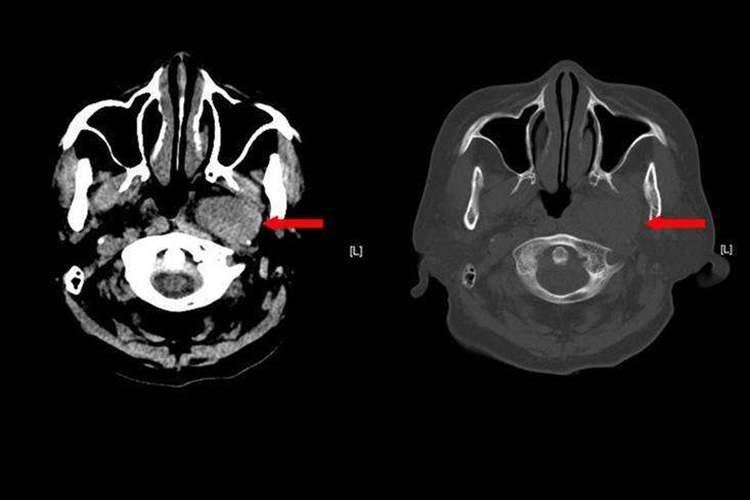

脊髓瘤多位于鼻咽,随着肿瘤增大,常有头痛、进行性鼻塞、脓性鼻涕、鼾声、嗅觉减退、耳鸣、耳聋等。发生于口咽者可有吞咽不适及出现呼吸困难。查体可见鼻咽顶壁、咽后壁、侧壁上有脓块隆起,基底广,触之稍硬,表面有正常黏膜。